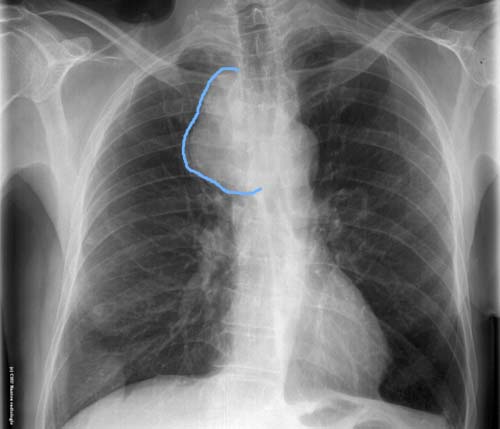

Syndrome médiastinal

Opacité du médiastin supérieur droit de tonalité hydrique homogène à limite externe nette se raccordant en pente douce avec les bords du médiastin : masse médiastinale refoulant l'arc supérieur droit ( tronc veineux brachiocéphalique et veine cave supérieure )